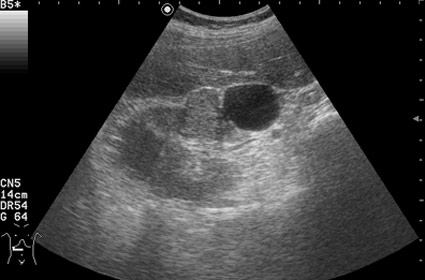

Поперечное серошкальное сканирование.

Обозначенный сегмент почки по структуре не отличим от рядом лежащих участков, выбухание контура над указанным сегментом тоже ни о чем не говорит, т.к. может быть просто дольчатостью.

Дольчатость почки в 56 лет?

При гистологии эта структура была почечно-клеточным раком (RCC).